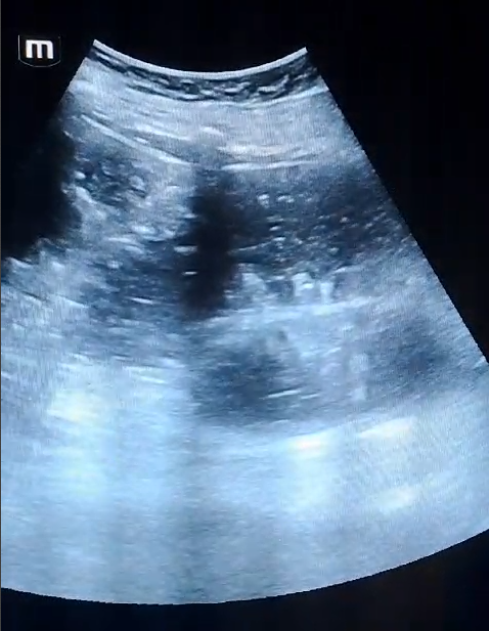

La paciente fue ingresada tras el diagnóstico de suboclusión intestinal. Se identificó mediante ecografía a pie de cama el signo de las «teclas de piano», característico de la obstrucción intestinal, lo cual orientó a un manejo conservador inicial. La paciente se mantuvo estable, sin signos de sufrimiento intestinal ni complicaciones mayores durante las primeras 24 horas. Se continuó con el manejo médico y se planificaron reevaluaciones frecuentes para monitorizar su evolución.

Este caso resalta la utilidad de la ecografía a pie de cama en el diagnóstico precoz de condiciones abdominales agudas como la suboclusión intestinal. En atención primaria, es fundamental reconocer signos ecográficos que permitan una evaluación rápida y precisa.